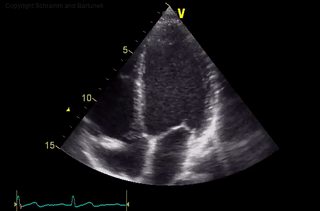

Bei der transthorakalen Echokardiographie wird das Herz durch Ansetzen des Ultraschallkopfes auf den Brustkorb untersucht.

Über die parasternale Schallkopfposition (meist über dem dritten bis fünften linken Zwischenrippenraum) kann die Längsachse und Querachse des Herzens eingesehen werden.

Über die apikale Schallkopfposition (meist über dem siebten bis neunten Zwischenrippenraum in der vorderen Axillarlinie) erhält man unter anderem einen 2-Kammer-Blick und 4-Kammer-Blick auf die Herzhöhlen.